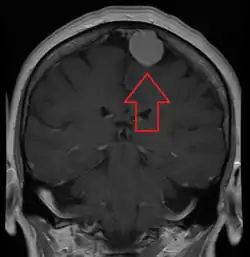

| An MRI of the brain, demonstrating the appearance of a meningioma | |

Meningiomas are visualized readily with contrast CT, MRI with gadolinium,[23] and arteriography, all attributed to the fact that meningiomas are extra-axial and vascularized. CSF protein levels are usually found to be elevated when lumbar puncture is used to obtain spinal fluid. On T1-weighted contrast-enhanced MRI, they may show a typical dural tail sign absent in some rare forms of meningiomas.[18]